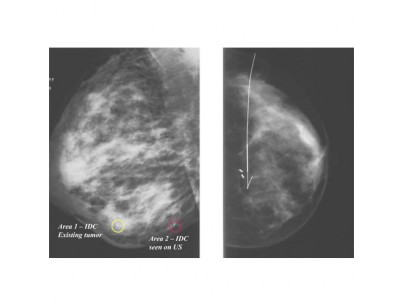

Permanent invasive breast site markers